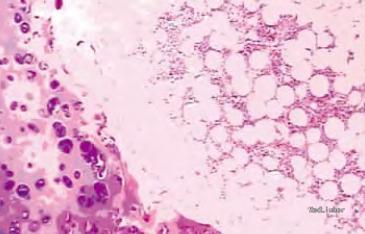

诊断、治疗:术前诊断为左侧甲状腺肿,行 双侧甲状腺次全切术,术中冷冻病理诊断为(左)甲状腺良性畸胎瘤。光镜下见左侧结节囊壁由柱状上皮、鳞状上皮和腺体构成,并含有成熟软骨,内部可见骨髓及脂肪组织。病理诊断为( 左)甲状腺成熟性囊性畸胎瘤。患者术后恢复良好。